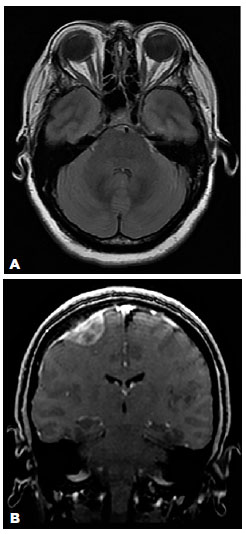

Neurological examination and extensive laboratory investigations were normal. Cranial magnetic resonance imaging (MRI) revealed flattening of the posterior pole of the OD and an empty sella, without ventricular enlargement or midline shift of the brain. There was a right frontal extra-axial mass with a tail sign at its dural base that was compatible with meningioma (Figure 3). There was no evidence of cerebral venous sinus thrombosis or stenosis. Lumbar puncture indicated an opening CSF pressure of 38 cmH2O with normal cytochemical analysis. A diagnosis of IIH with an incidental meningioma was accordingly made.

13-fig03.jpg)